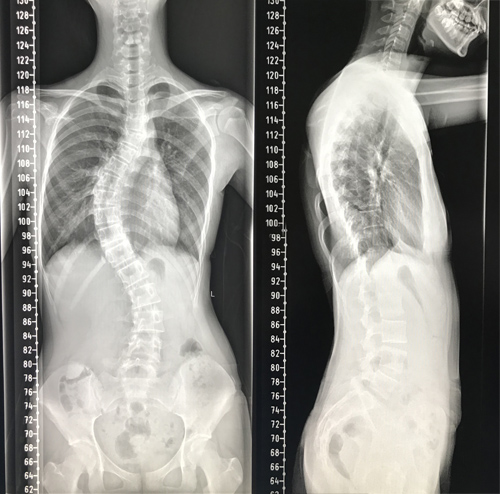

患者小冰今年13岁,4个月前家属发现小冰肩背部明显不对称,严重影响美观,且无法平卧入睡,经多方咨询,慕名来临床医学院/附属医院骨三科就诊。专科检查发现患者脊柱呈明显S型弯曲,躯干向右侧倾斜,双肩不等高,剃刀背畸形,主胸弯Cobb角度达60°,脊柱畸形较为严重。该院骨三科朱述浪主任带领脊柱外科团队,详细讨论了小冰的病情。

术后护理团队制定了详细的护理计划,严密观察患者生命体征及切口情况。在科室全体医护人员的共同努力下,小冰术后各项指标恢复良好,术后68小时便拔除引流管,并佩戴支具下床活动。复查脊柱全长片提示脊柱S型弯曲得到了充分矫正,双肩等高,剃刀背畸形消失。术后,小冰终于可以正常平卧睡觉,而且身高达到164.5cm,较术前足足增高了4.5cm。